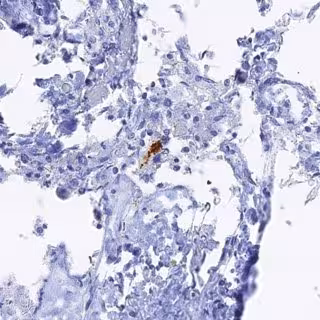

En este sentido, el estudio ha descrito un evento clave en el proceso de necroptosis que es cuando RIPK1 y RIPK3 forman una estructura filamentosa conocida como necrosoma, la cual parece que da comienzo al proceso de necroptosis.

A continuación, identificaron la cascada molecular de la activación de necroptosis, con RIPK1 activando a RIPK3. Este complejo proteico se une y activa MLKL. Concretamente, el análisis de ARNm y proteína reveló niveles elevados tanto de RIPK1 como de MLKL en los tejidos cerebrales 'post mortem' de pacientes con Alzheimer, en comparación con los cerebros 'post mortem' normales.